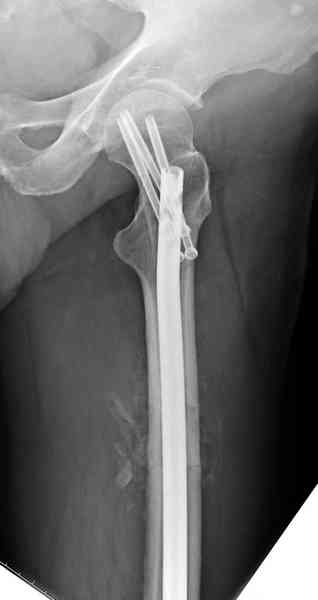

Здесь представлены снимки больного 65 лет, поступившего с диагнозом перелом

бедра после автоаварии.

В первый же день произведено антеградное штифтованием DePuy Trochanteric Nail.

На второй день (7) обнаружен пропущенный перелом,

сделаны Компьютерная Томограмма

и проведены шурурпы через и спереди штифта без удаления.

Послеоперационные снимки